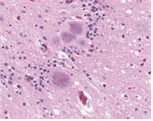

typical amyloid plaques found in a case of variant Creutzfeldt-Jakob disease (vCJD)

출처:http://phil.cdc.gov/phil/details.asp ID#10130, CDC/Dr. Fred Murphy; Sylvia Whitfield